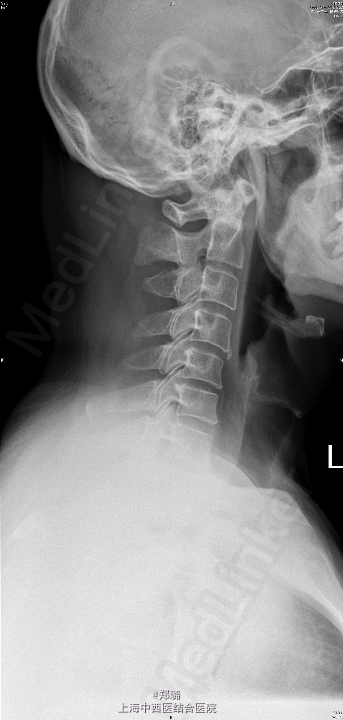

查体:神志清晰,精神尚可,呼吸平稳,营养中等,表情自如,发育正常,自主体位,应答流畅,查体合作。全身皮肤无黄染,无肝掌、蜘蛛痣。全身浅表淋巴结无肿大。脊柱无畸形,生理曲度变直,压颈试验(+),臂丛牵拉试验(+),右肩颈部疼痛,右上臂、前臂桡侧、手部刺痛觉迟钝,双Hoffmann征(-),双侧Babinski征(-);双侧Chaddock征(-),双侧肱二头肌腱膜反射可疑亢进,双侧膝反射正常,四肢肌力尚可。 辅助检查: 外院:CT及MRI(2015-5-19)示:C5/6椎间盘突出,C4/5椎间盘轻度突出 颈椎过伸过屈侧位X线【2015-05-22】 :颈椎动力位未见明显椎体滑脱征象。 颈椎正位(前后位)、侧位X线【2015-05-22】 :颈椎退行性变

随访讨论: 1.注意休息,保持伤口清洁干燥; 2.遵医嘱适当颈部功能锻炼 3.术后2月,半年,1年,2年均需返院复查; 4.我科随诊。 X线术后:颈椎术后,C5、6见金属内固定影,相应椎间隙内见填充物影, 颈椎顺列正常,生理曲度存在,中下段椎体边缘稍有骨质增生变尖,椎间隙无狭窄,未见骨破坏及异常软组织影。